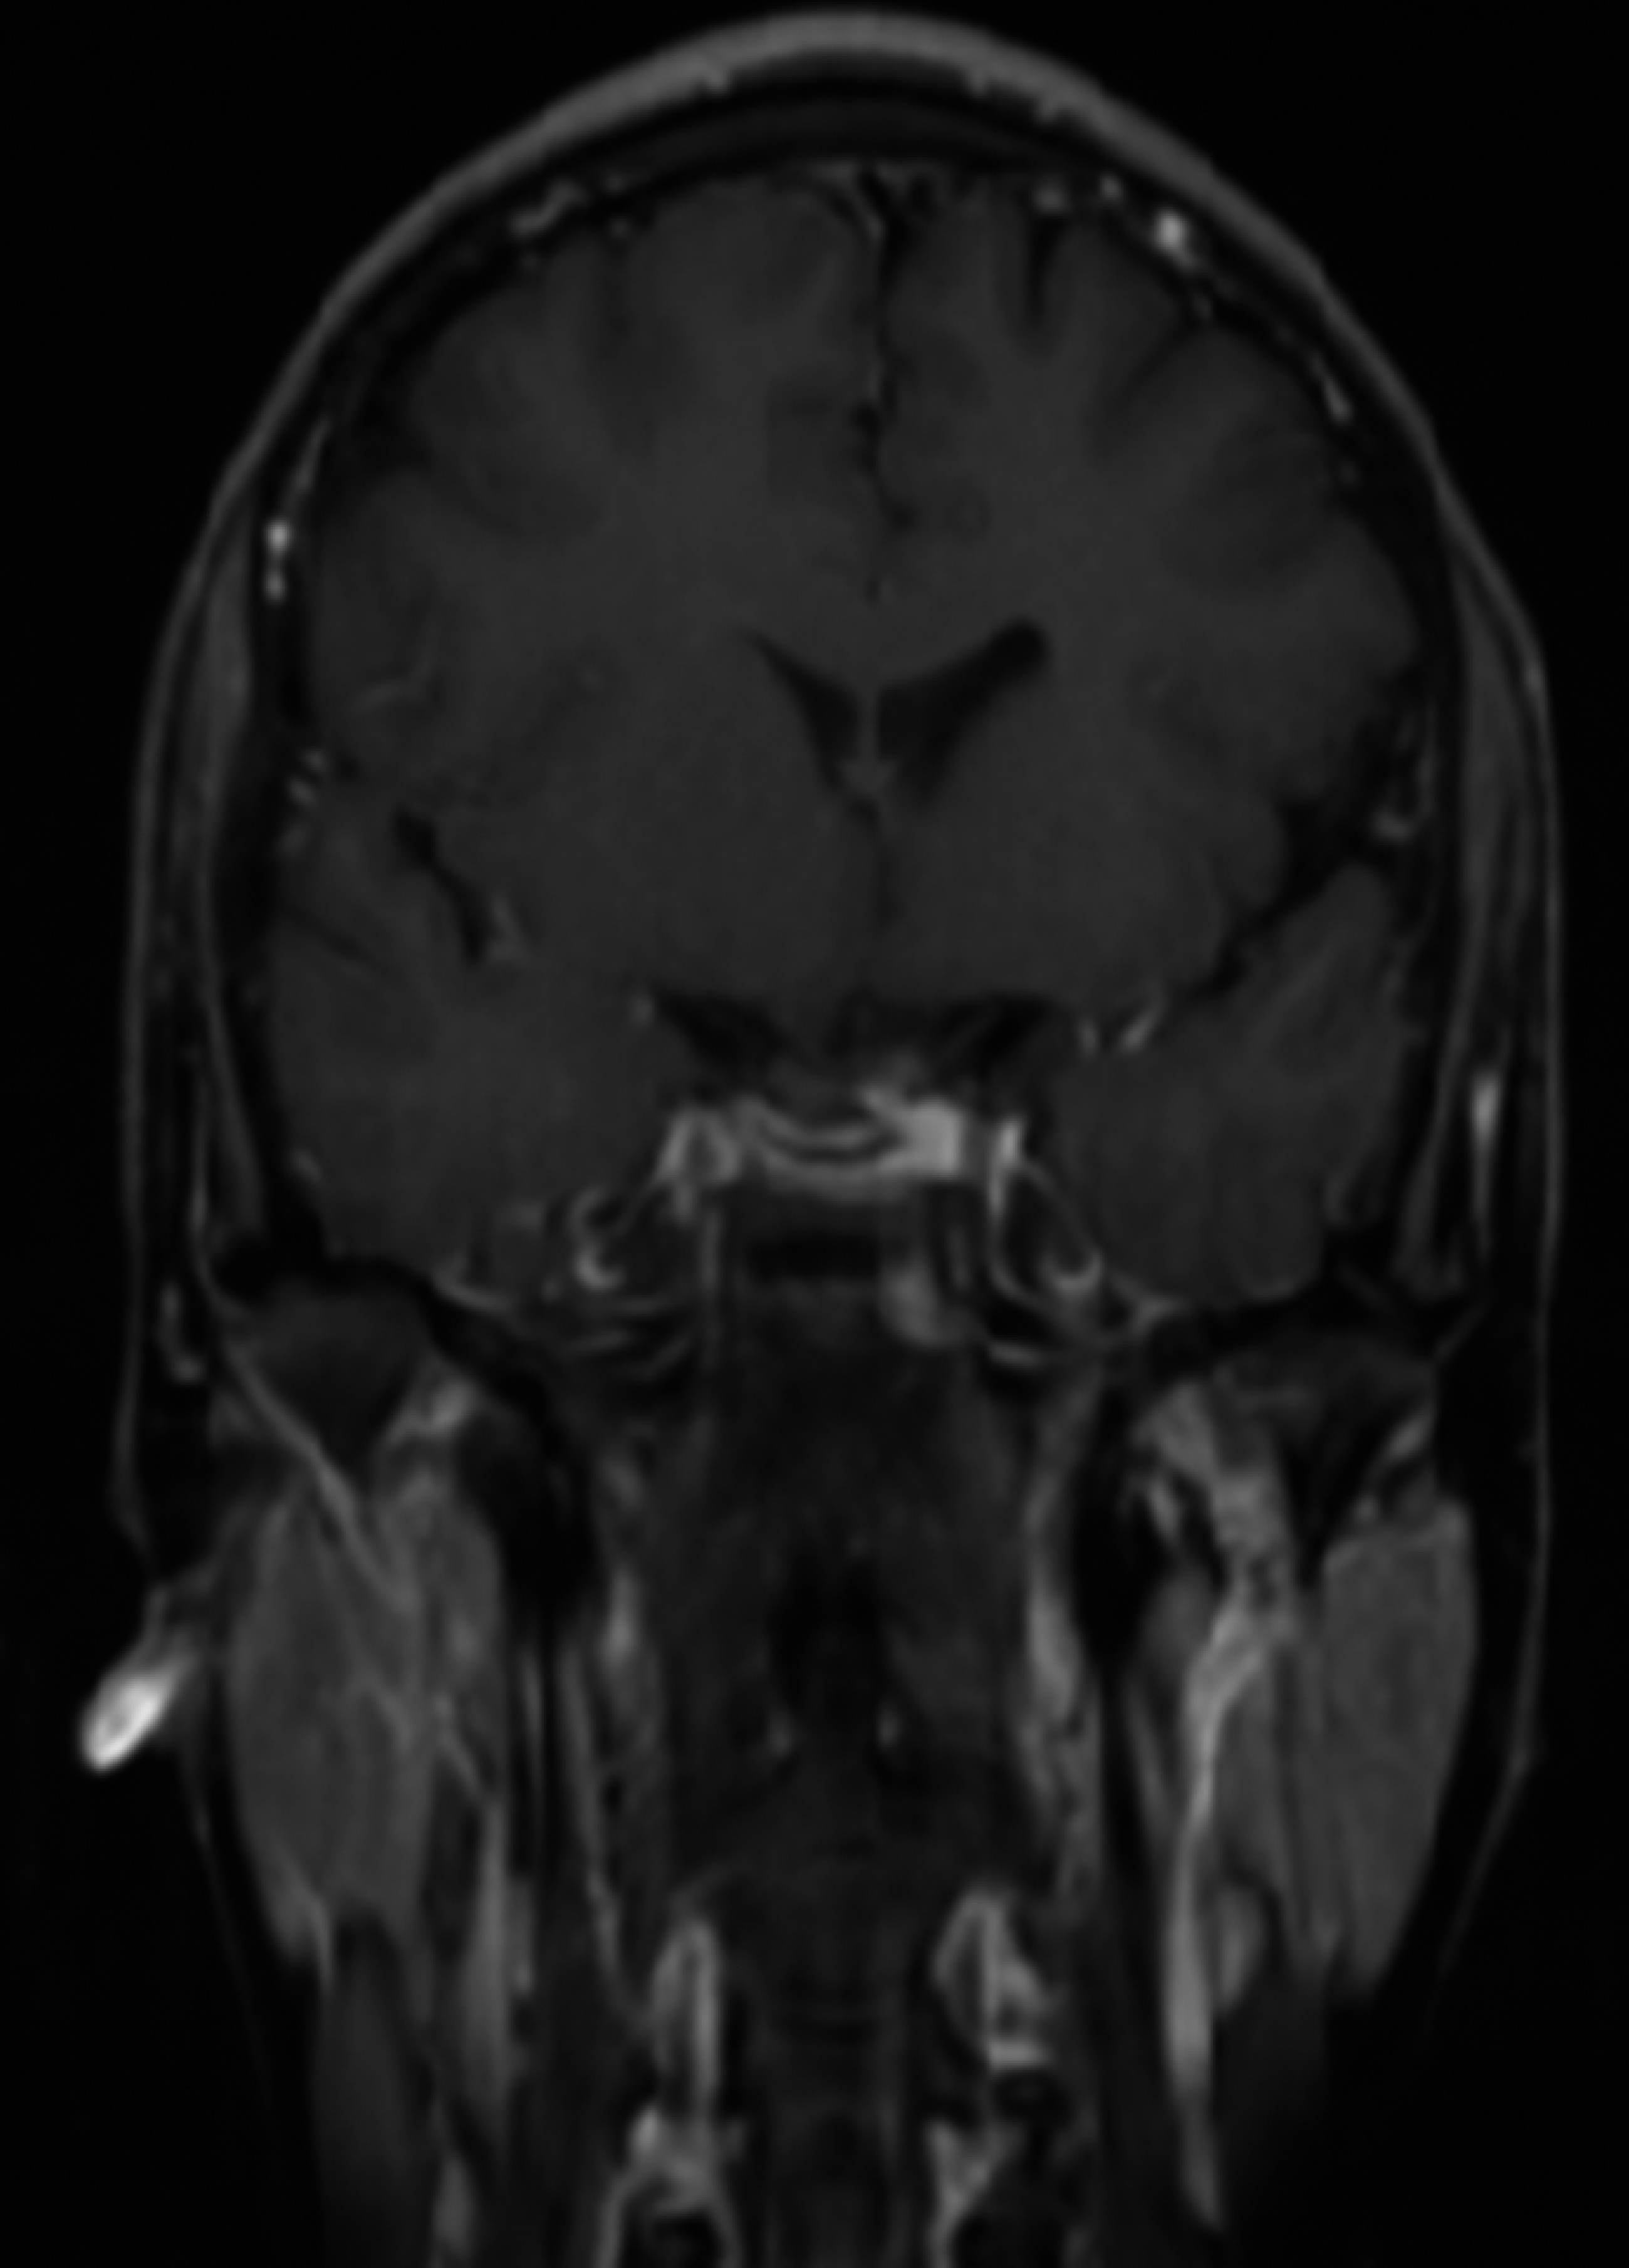

Se realizó resonancia magnética de cráneo ponderada en T1 y T2, T1 contrastado con gadolinio detectó lesión selar de bordes bien definidos, isointenso en relación con parénquima cerebral con realce en anillo tras administración de gadolinio, con diámetro 22 × 37 × 28 mm, se extiende hacia región supraselar sin compresión del tercer ventrículo, el resto sin alteraciones (Figura 1).

Figura 1